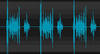

Holosystolic Murmur

- A holosystolic murmur begins at the first heart sound (S1) and continue to the second heart sound (S2), as illustrated in the phonocardiogram.

- Typically high-pitched, these murmurs are usually caused by ventricular septal defect, mitral regurgitation or tricuspid regurgitation, as discussed below

- A heart murmur between S1 and S2 is a systolic murmur. There is turbulent blood flow during ventricular contraction, that is, the time elapsing between atrioventricular and semilunar valvular closure.

- If the murmur is louder than S1 and S2, and extends throughout the whole of systole, which defines it as loud and holosystolic, respectively. The most common cause of a loud holosystolic murmur with point of maximal intensity over the left cardiac apex is mitral regurgitation.